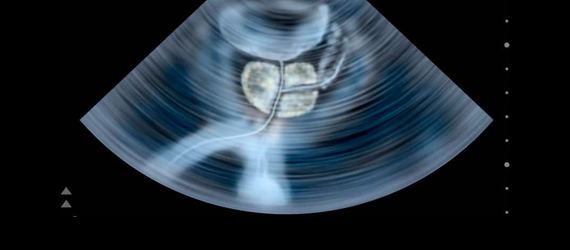

Ecografía Prostática

Con la ecografía prostática obtenemos imágenes de la glándula prostática y tejidos circundantes en el hombre.